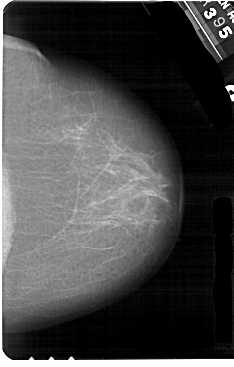

A_1266_1.RIGHT_MLO

RIGHT_MLO LINES 5491 PIXELS_PER_LINE 3601 BITS_PER_PIXEL 12 RESOLUTION 43.5 NON_OVERLAY